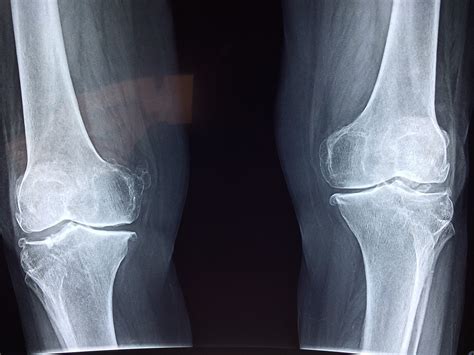

Common Findings in Knee X-rays

Knee X-rays can reveal a variety of conditions. Some of the most common findings include:

• Fractures: Breaks in the bone, which can range from small cracks to complete breaks.

• Arthritis: Degenerative changes in the joint, such as narrowing of the joint space and bone spurs.

• Dislocations: Misalignment of the knee joint, often due to trauma.

• Bone Spurs: Extra bone growths that can cause pain and limit mobility.

• Tumors: Abnormal growths that can be benign or malignant.